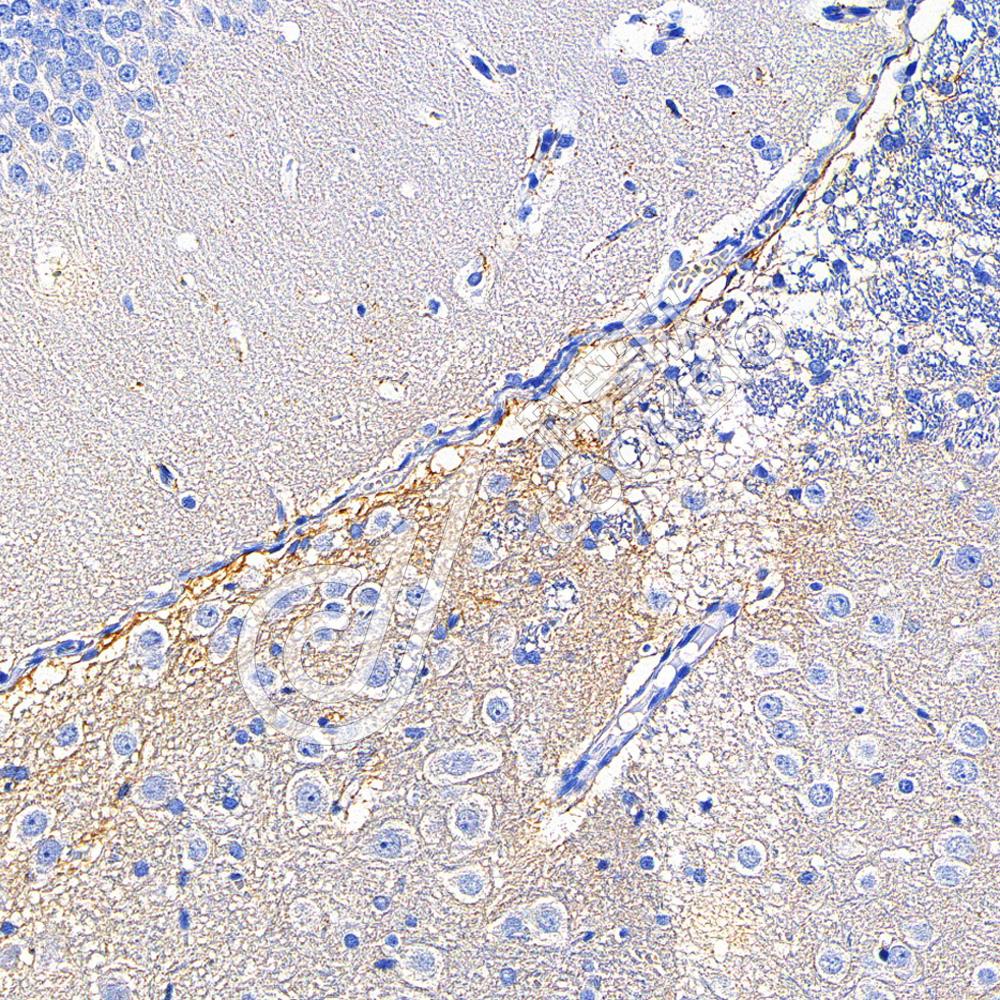

IHC检测PSMA蛋白(货号 K1347130).

样品: 大鼠脑, 4%多聚甲醛 (货号KSG1101) 固定12-24小时.

抗原修复: 柠檬酸抗原修复液(干粉, pH 6.0) (KSG1201), 高压锅均匀喷气计时2分钟.

—抗: 1: 300稀释, 4℃ 孵育过夜.

二抗: S-vision免疫组化多聚二抗(山羊抗兔),即用型 (货号KB3906), 室温孵育20分钟.